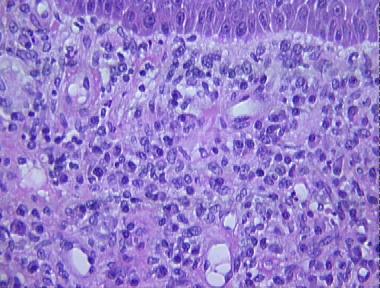

granuloma inguinale

Histologic Features